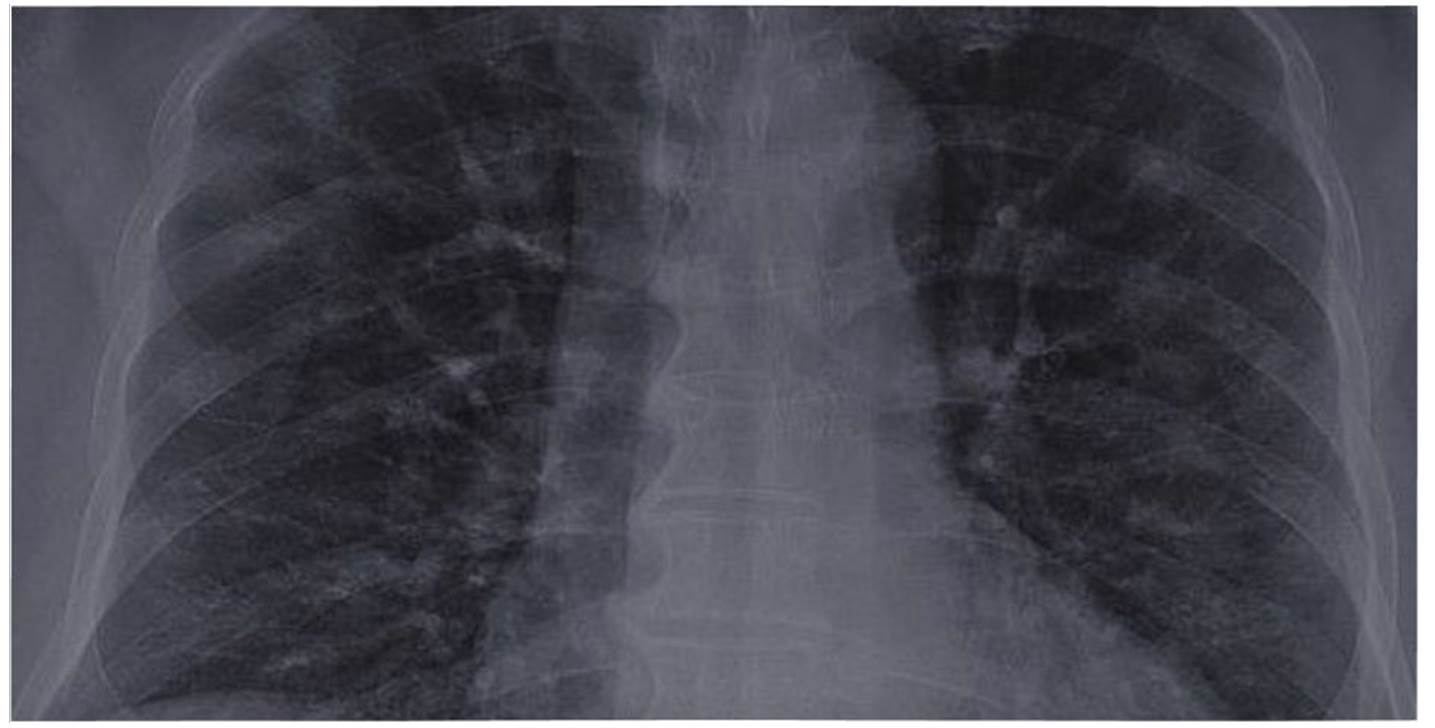

El objetivo principal de la infección por COVID-19 es el tracto respiratorio inferior, causando neumonía grave combinada con evidencias radiológicas de opacidades en vidrio esmerilado 17,37. En la figura 1 se describe una neumonía por COVID-19. Las partículas del virus se propagan a través de la mucosa respiratoria, infectando otras células, e induciendo una tormenta de citoquinas a nivel sistémico, lo cual genera una serie de respuestas inmunes y causan cambios en los leucocitos periféricos (linfocitos) 1.